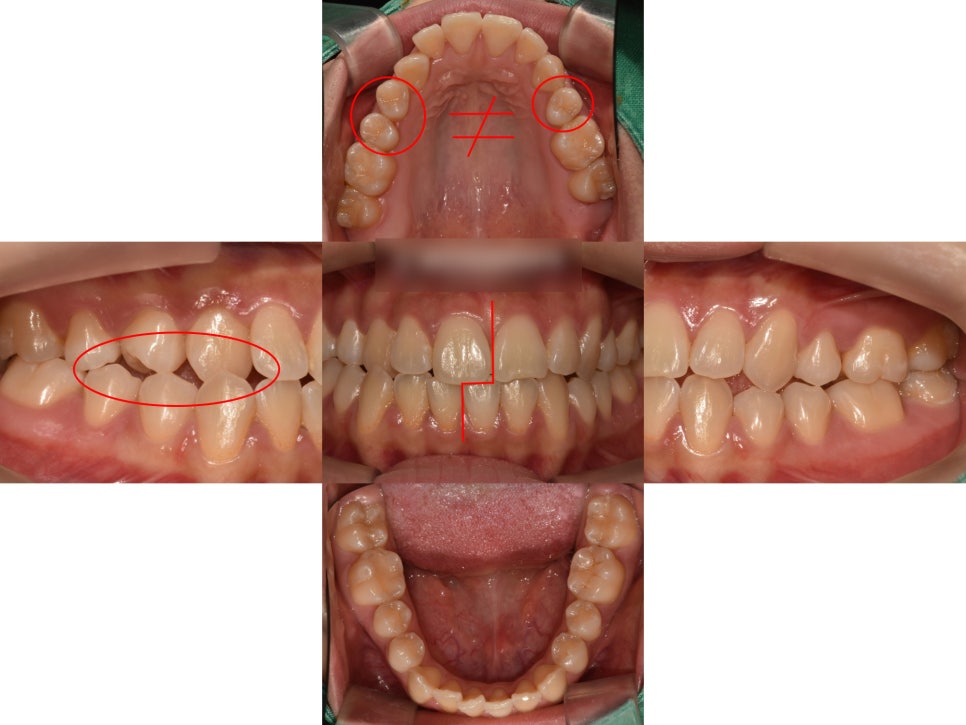

『1. 급속구개확장장치를 통한 위턱 확장 (MARPE)

먼저, 윗니가 아랫니를 충분히 덮어줄 수 있도록

위턱을 확장시키는 작업을 진행했습니다.

(MARPE 장치 사용)

어느정도 위턱이 확장되면서

공간이 조금씩 생기기 시작할때,

상악 확장이 잘 이루어져

윗니가 아랫니를 덮을 수 있는

상태가 되었습니다.